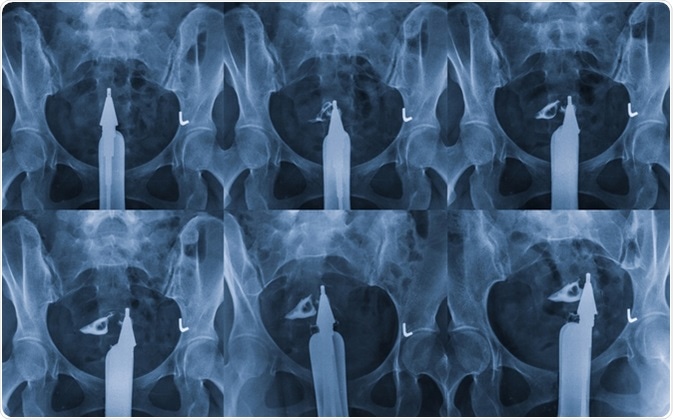

Hysterosalpingography is a type of X-ray called fluoroscopy that looks at a woman's uterus and fallopian tubes. Image Credit: MossStudio / Shutterstock